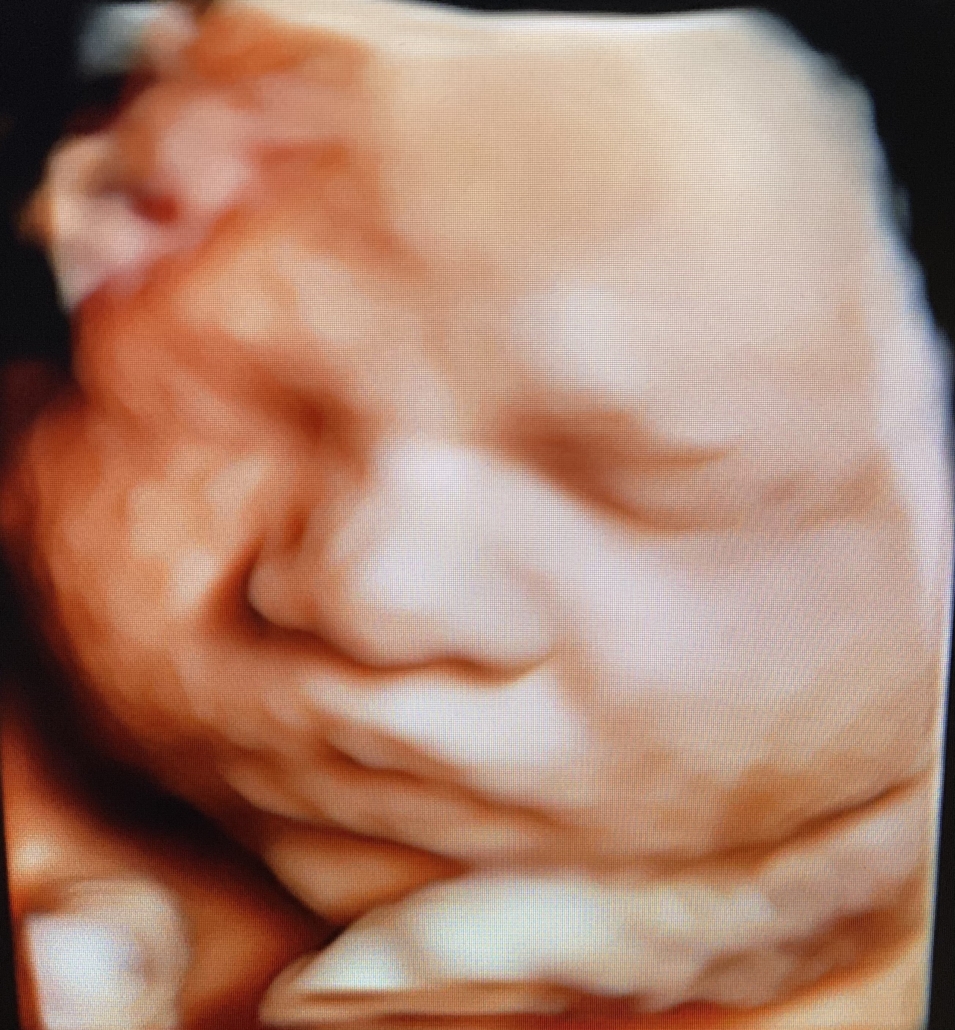

Prenatal Peek®

Prenatal Peek is the leader in 3D 4D Ultrasound. We employ only Certified / Registered Sonographers maintaining unsurpassed standards in 3D ultrasound. You deserve the best! Call us today.